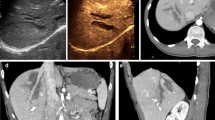

Changes in CEUS perfusion features with shock progression

In the pre-shock state, CEUS PI was rapidly observed in the interlobar artery, arcuate arteries, renal cortex, and medulla after injection of the ultrasound contrast agents, and the values then returned to the baseline levels during 9.63 ± 0.41 s. With the progression of shock, the PI declined slowly, while the TTP and WT increased. During mild shock, AT and TTP exhibited the earliest changes, and these changes became more pronounced with increasing degrees of shock. In cases of moderate and severe shock, PI began to decline, while WT became significantly prolonged (Fig. 2a–d).

Shock causes a series of physiological reactions, including a sharp reduction in renal blood flow, reduced glomerular filtration rate, intracellular acidosis, adenosine triphosphate consumption, and enhanced activity of the renin–angiotensin–aldosterone system. This cascade leads to contraction of the renal vascular bed and release of catecholamines into the blood [16, 17]. Renal cortical blood vessels are abundant in sympathetic fibers with adrenaline receptors, which are particularly sensitive to catecholamines. After injection of a US contrast agent, time–intensity curves can be calculated to quantitate microcirculation perfusion [17]. In the present study, we found that the AT and TTP after injection of the contrast agents were delayed at various stages of shock, possibly because the contrast medium was obstructed by renal vascular contraction. However, PI did not change significantly during mild shock, suggesting that it is not a sensitive indicator. During early shock, renal cortical perfusion is maintained to guarantee the function of other important organs such as the heart and brain [18]. With the progression of ischemia, the high secretion of angiotensin and endothelin would cause renal tissue damage but could also increase afferent and efferent arteriolar resistance. As a result, renal cortical blood perfusion decreases progressively, the number of microbubbles in the renal cortex is reduced, and the reflection backscatter signal deceases. Correspondingly, cortex echo intensity is significantly decreased. An important observation of the present study was the decreased PI with increased AT and TTP with shock progression. Moreover, WT was prolonged, suggesting that the capillary bed was constricted. These manifestations can help to predict the occurrence and progression of hemorrhagic shock. On the other hand, they may also affect the evaluation of traumatic lesions by CEUS because they can lead to reduced contrast between the traumatic lesion and the surrounding splenic tissue.